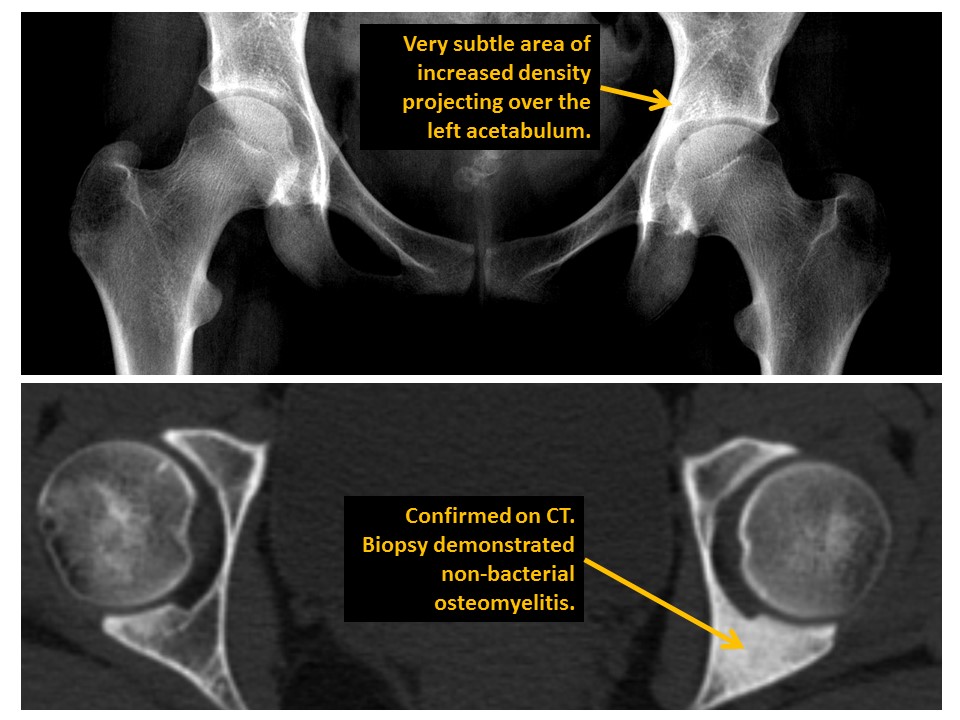

INNOMINATE BONES

There are cortical disruptions, displaced fractures, or avulsion fractures. [Yes/No]

Triradiate cartilages are asymmetric. [Yes/No]

Acetabular fractures are present. [Yes/No]